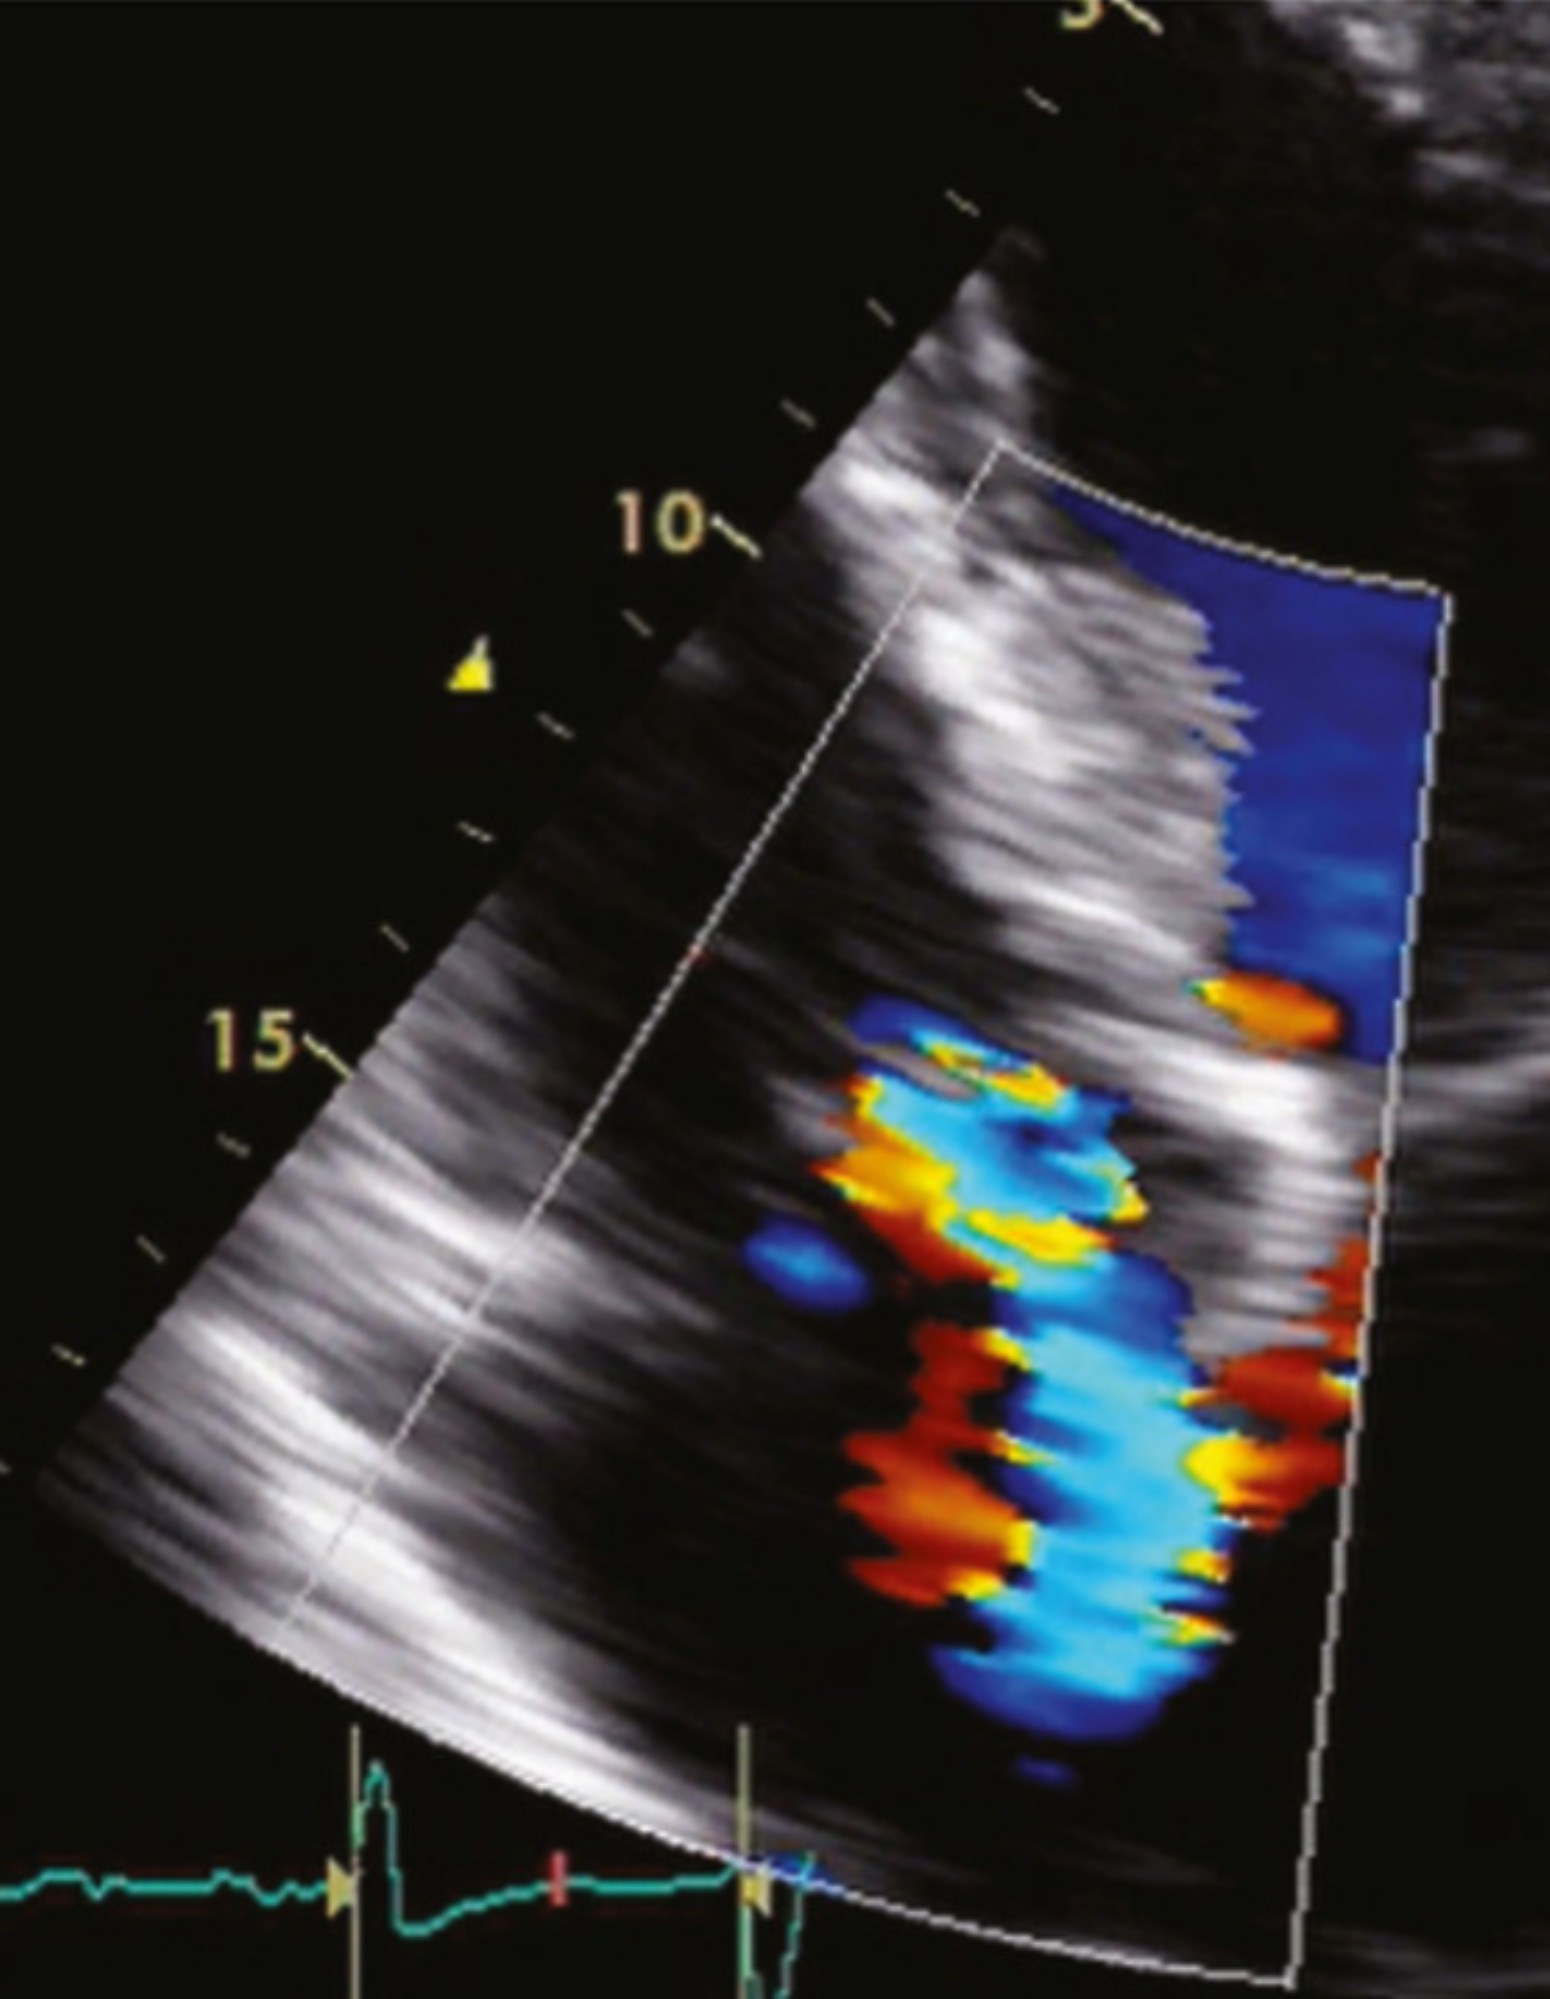

Hình ảnh hở van tim 3 lá 2/4

Để hiểu thêm về tình trạng hở van tim 3 lá 2/4, bạn có thể theo dõi một số hình ảnh dưới đây:

Van 3 lá hở 2/4 khiến máu rò rỉ ngược lại nhĩ phải. – Ảnh: Internet.Hình ảnh siêu âm hở van 3 lá 2/4. – Ảnh: Internet.